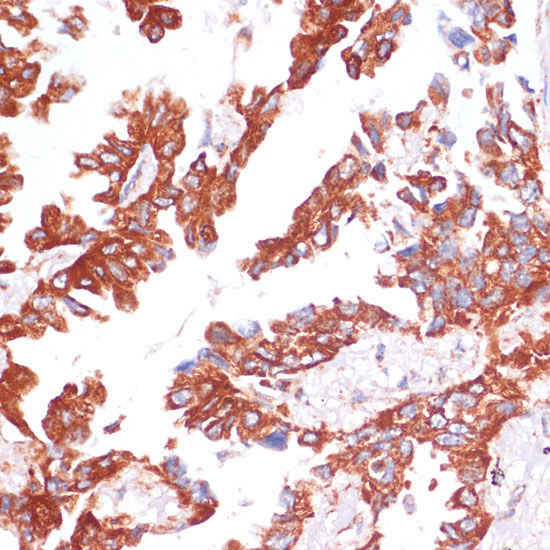

Immunohistochemistry of paraffin-embedded human lung cancer using Caspase-9 antibody at dilution of 1:100 (40x lens).